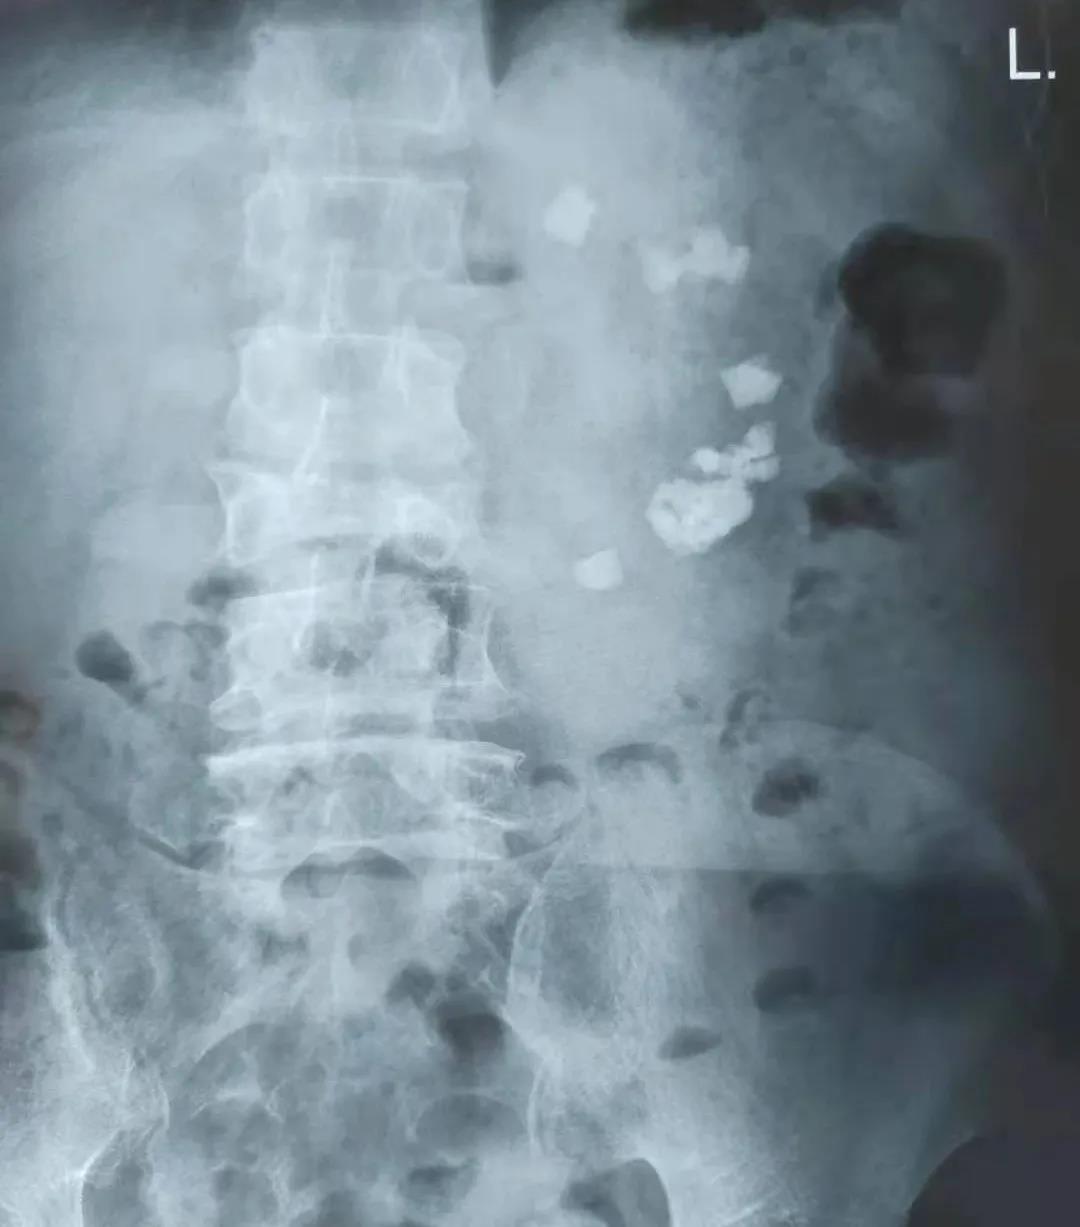

崔先生的左腎結(jié)石病史已有30多年,20余年前曾在外院進(jìn)行左腎切開(kāi)取石手術(shù)治療,但是10余年前在定期查體時(shí)卻發(fā)現(xiàn)左腎結(jié)石已再次復(fù)發(fā)。出于對(duì)手術(shù)的抗拒,崔先生一直默默忍受著結(jié)石帶來(lái)的疼痛和不適,并且飽受著結(jié)石引發(fā)的反復(fù)泌尿道感染的折磨。直至最近,崔先生出現(xiàn)了左輸尿管的結(jié)石梗阻,變本加厲的疼痛使他苦不堪言。經(jīng)朋友推薦,崔先生懷著忐忑不安的心情來(lái)到了濰坊市市立醫(yī)院。經(jīng)過(guò)全面檢查,發(fā)現(xiàn)患者的左腎結(jié)石數(shù)量極多,且分布松散,幾乎上中下所有腎盞中都有結(jié)石,而且患者有開(kāi)放手術(shù)史,腎臟原有的結(jié)構(gòu)已經(jīng)遭到了破壞,腎周還與周圍的腸管發(fā)生了黏連,這無(wú)疑增加了手術(shù)的難度和風(fēng)險(xiǎn)性。

患者術(shù)前腹部平片

經(jīng)過(guò)全面細(xì)致的術(shù)前準(zhǔn)備,副院長(zhǎng)、泌尿外科主任解魯明為崔先生分期實(shí)施了經(jīng)尿道輸尿管鏡左輸尿管結(jié)石碎石取石術(shù)+經(jīng)皮腎鏡左腎結(jié)石碎石取石術(shù)。在解院長(zhǎng)的妙手醫(yī)術(shù)和團(tuán)隊(duì)的默契配合下,手術(shù)十分順利,崔先生術(shù)后疼痛輕微、感覺(jué)良好,身體恢復(fù)很快,已于不久前康復(fù)出院。